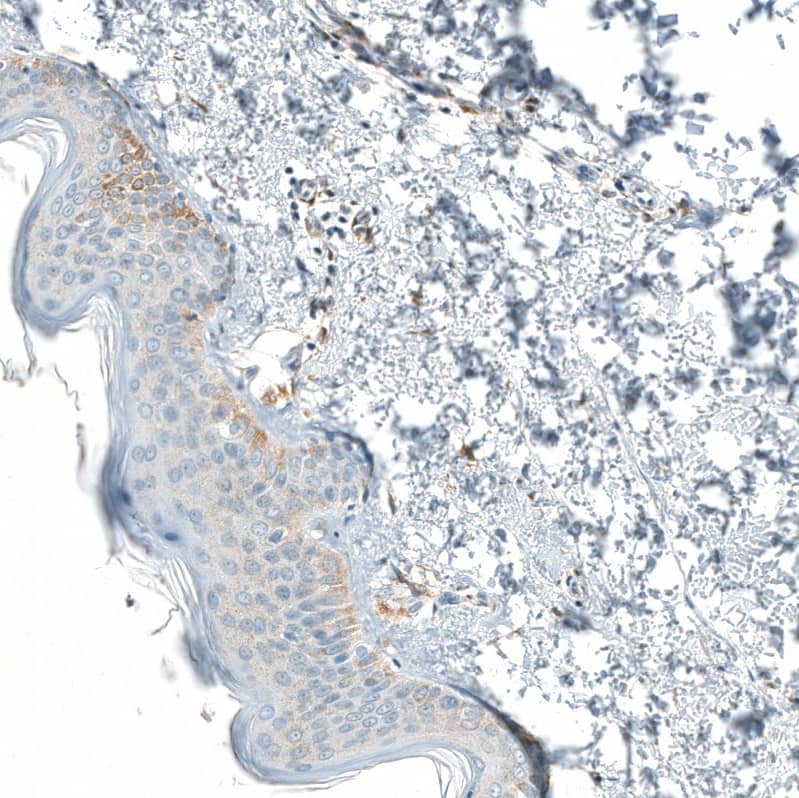

Staining of human skin shows very weak positivity in squamous epithelial cells.